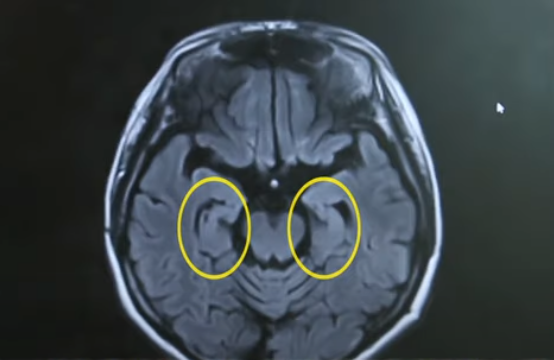

치매 환자의 65~70%는 뇌세포의 노화로 생기는 신경학적 퇴행성 질환인 알츠하이머 치매를 앓고 있습니다. 이는 베타 아밀로이드와 타오라는 단백질이 뇌에 쌓여 뇌 기능 감소로 발생되는 노인성 치매입니다. 알츠하이머 치매는 진단을 위해서 알츠하이머 치매의 원인인 베타 아밀로이드가 뇌 속 어느 부위에 쌓여 있는지 영상으로 확인하기 위해 아밀로이드 펫 검사를 진행합니다. 이는 머리에 아밀로이드가 있는지 없는지를 확인하는 것으로 아밀로이드 펫 검사에서 양성으로 나오게 되면 알츠하이머 치매가 향후 점점 더 진행될 것이라 예상할 수 있습니다. 뿐만 아니라 해마 손상 정도를 보고 알츠하이머 치매를 예측할 수 있습니다.

위 사진과 같이 해마에서 위축이 있다는 것은 기억이 떨어졌다는 것을 의미하며 이럴 경우 치매 중에서도 알츠하이머 치매가 가능성이 높다는 것을 알 수 있습니다.